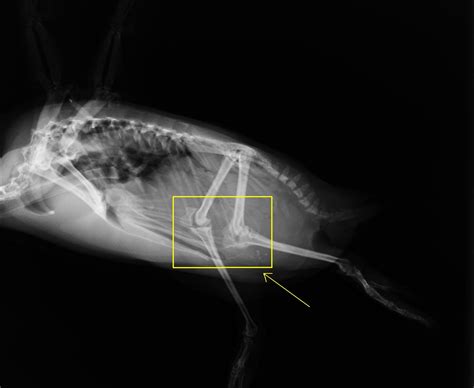

Yes, penguins do have knees, but they are not visible from the outside. The knees are located high up on the body, hidden beneath the feathers and skin. This unique adaptation allows penguins to move efficiently in the water while still being able to walk on land, albeit in a waddling manner.

The hidden knees of penguins are a result of their evolutionary adaptations. Over millions of years, penguins have evolved to become highly specialized for aquatic life. Their legs are positioned far back on their bodies, which helps them swim faster and more efficiently. However, this adaptation also means that their knees are not visible from the outside, leading to the misconception that they do not have knees at all.